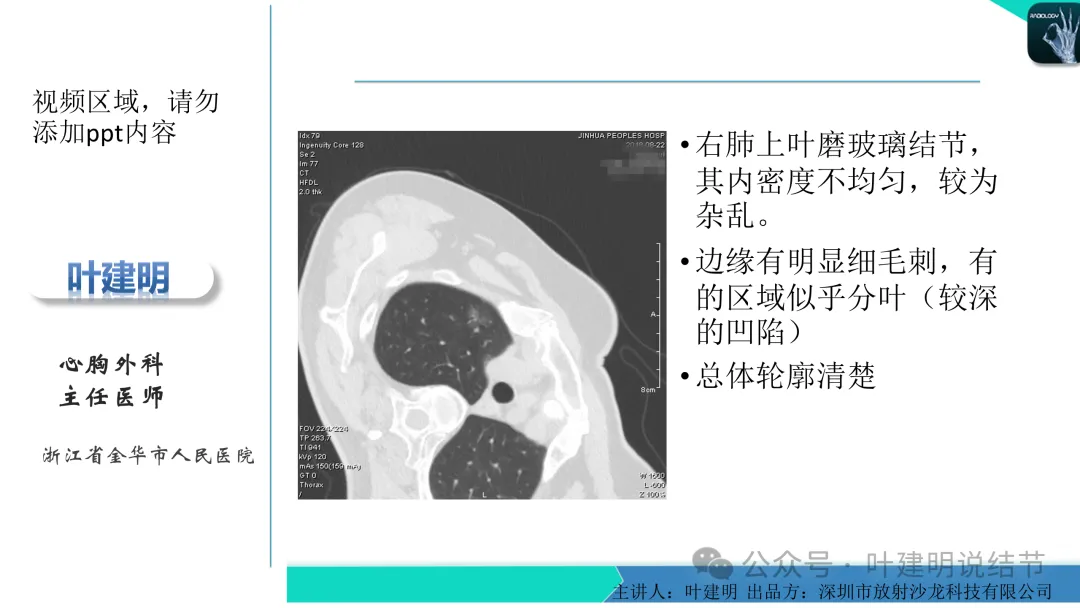

早在2020年时,我受邀在《放射沙龙》做过一个系列的精品课,当时专门总结分析过各类良恶性肺结节与肿块的影像特征,这是当时关于微浸润性腺癌影像特征的分析,今天看来仍基本不太需要改变,大家有兴趣的可以参考: